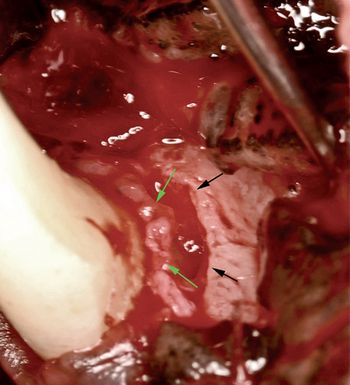

The lower jaw of the cat on your exam table is displaced to the left (Photo 1). Is the mandible or maxilla fractured? Or is the mandible luxated? If so, right or left? What is the best way to diagnose and treat this problem? Can you as a general practitioner handle it, or must the case be referred to a boarded orthopedic or dental specialist?